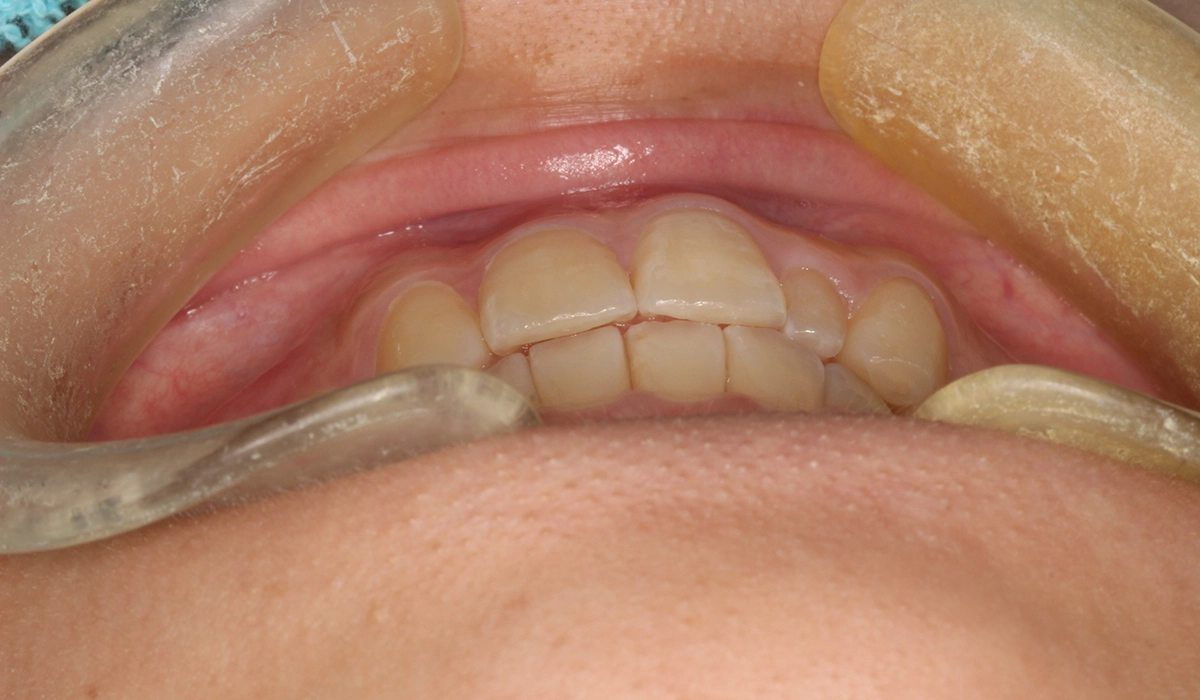

術前:オーバージェット

術後:オーバージェット